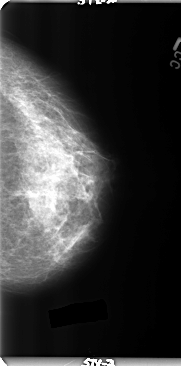

B_3156_1.LEFT_MLO

LEFT_MLO LINES 4760 PIXELS_PER_LINE 2680 BITS_PER_PIXEL 12 RESOLUTION 50 NON_OVERLAY